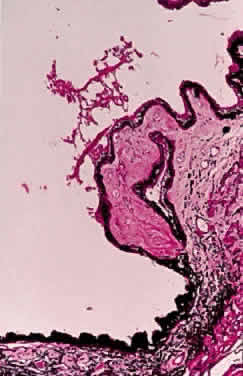

Exfoliative material frequently is observed at the pupillary border (Fig. 4) and should suggest the diagnosis of exfoliation even before the pupil is dilated.27 In addition, defects of the pigmented pupillary ruff are commonly seen. Aasved reports pupillary defects in 6.1% of eyes without XFS and in 74% of eyes with XFS.50 He further notes that in patients with unilateral XFS, pupillary ruff defects were twice as common in the affected eyes when compared with the fellow eyes. Iris transillumination defects in a moth-eaten pattern often are observed. Although these generally are limited to the region of the sphincter (Fig. 5), several patients also have diffuse midperipheral defects.51

Exfoliative material also may be observed histopathologically on the pupillary border,8 on the anterior iris surface77, within the anterior iris stroma, around iris blood vessels,78–80 and on the posterior surface of the iris.3,4 The iris has been implicated as a source of the material,73,81 and essentially all iris cell types, including epithelial cells, fibrocytes, melanocytes, vascular endothelial cells, pericytes, and smooth muscle cells, may be involved in the production of exfoliative material.55 Exfoliative deposits also have been described on the zonules and ciliary processes (Fig. 12) and within the basement membrane of the nonpigmented ciliary epithelium.4,82 Observations by Mizuno and Muroi suggest that exfoliative material may accumulate on these structures before deposition elsewhere in the eye.12